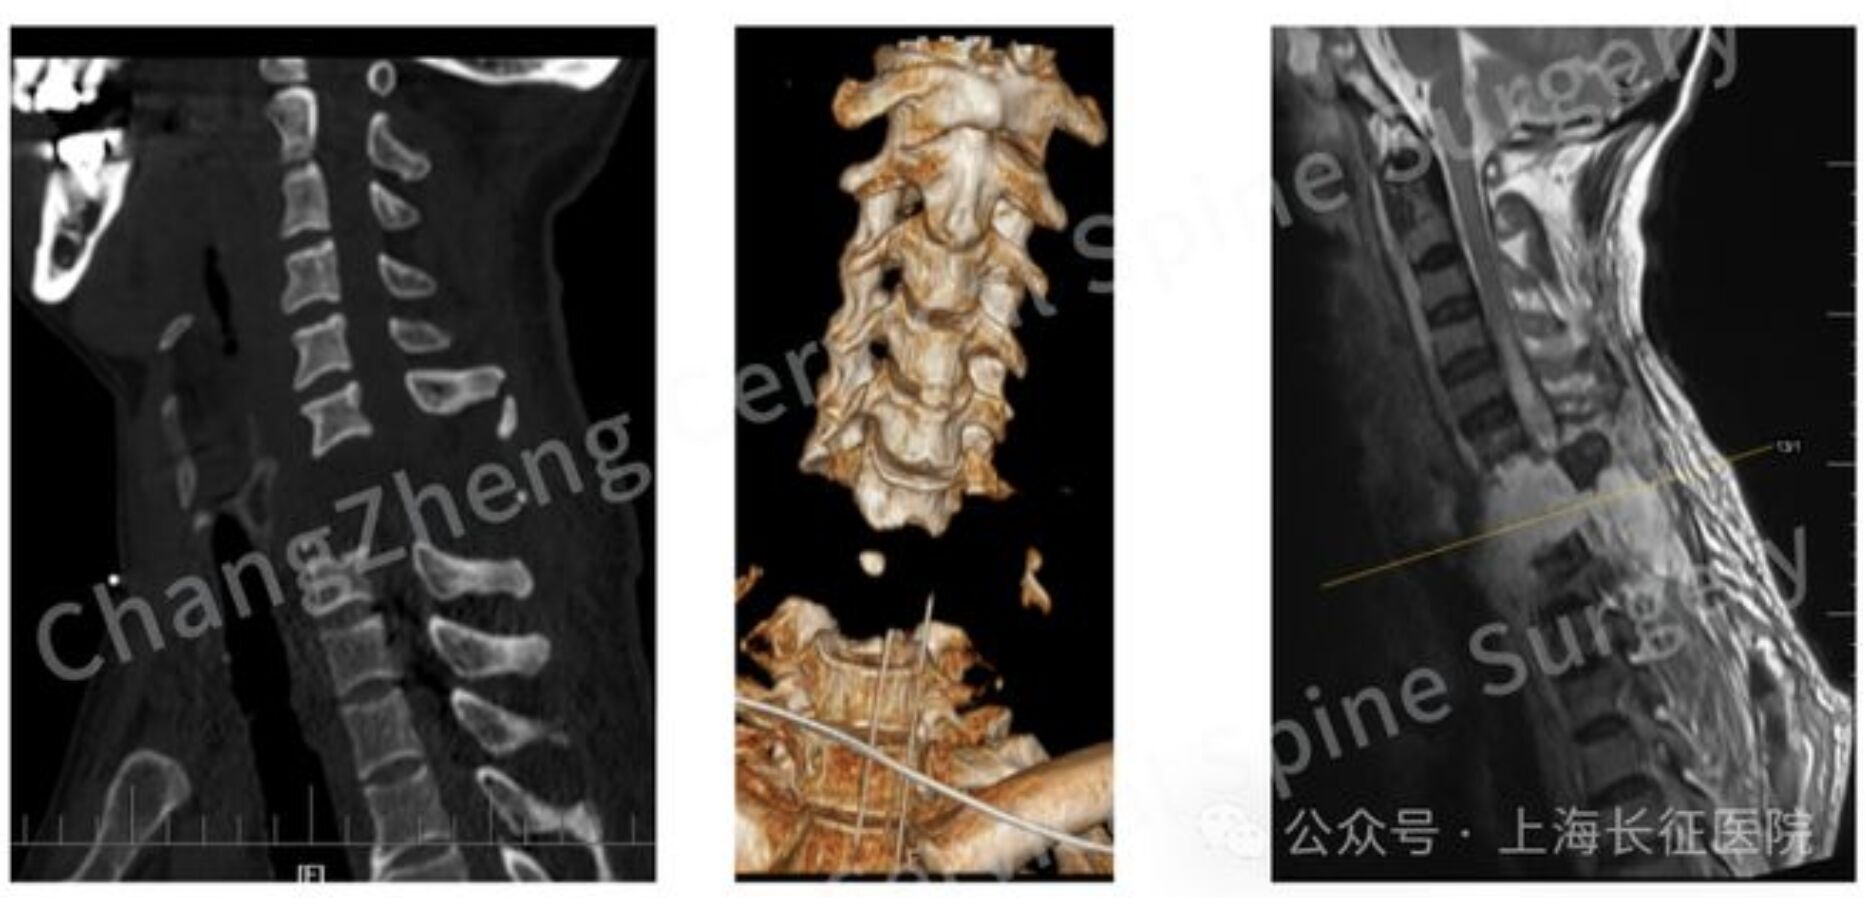

▲一名遭機械臂重擊的患者脊椎斷裂如同「斷頭」。(圖/翻攝上海長征醫院,下同)

上海長征醫院近日成功救回一名「頸椎斷開」的重傷患者。透過釋出的X光片可以發現,患者頸椎嚴重脫位的程度,幾乎等同於「斷頭」般的「首身分離」,原本被判定毫無生機,但在該院多學科團隊醫師的合作下奇蹟存活。主治醫師、長征醫院頸椎外科病區主任陳華江坦言,從醫近30年,這是首次遇到如此凶險病例。

《瀟湘晨報》報導,當時,患者因頸部遭受機械臂重擊,導致頸椎瞬間遭受毀滅性損傷,當場高位截癱、心跳驟停,經緊急心肺復蘇才勉強恢復微弱生命體徵。影像學檢查結果令人震驚,頸椎發生極其罕見的大跨度脫位,其嚴重程度猶如「身首離斷」,已造成脊髓嚴重挫傷、關鍵神經血管結構撕裂。